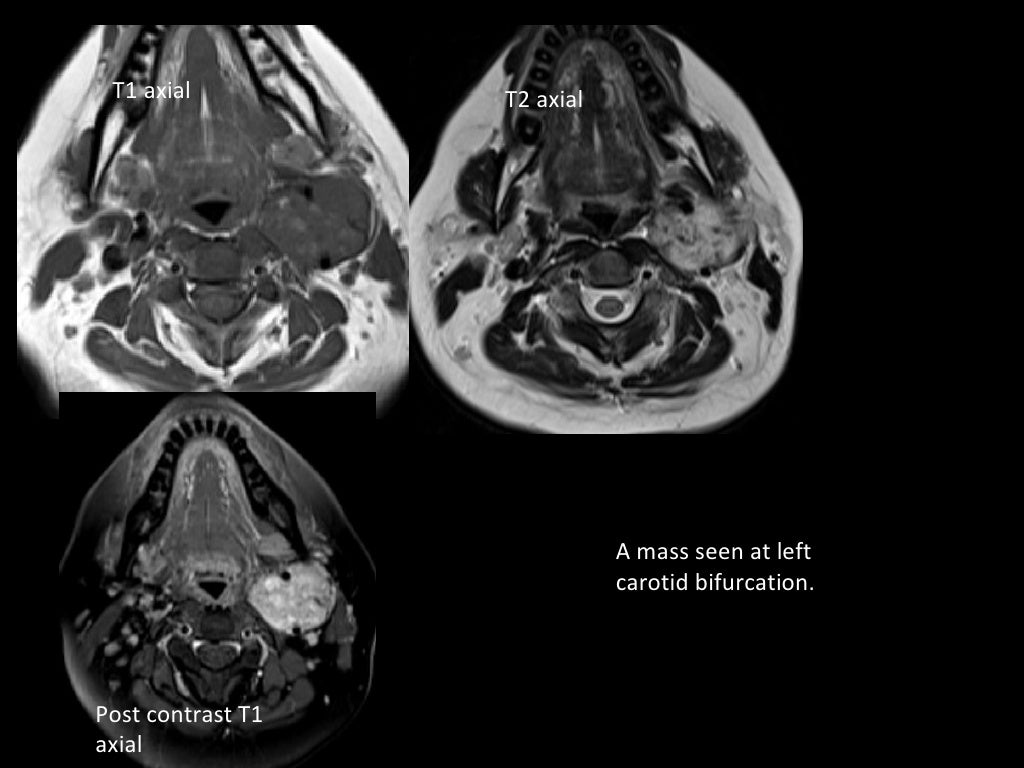

MRI in neck imaging